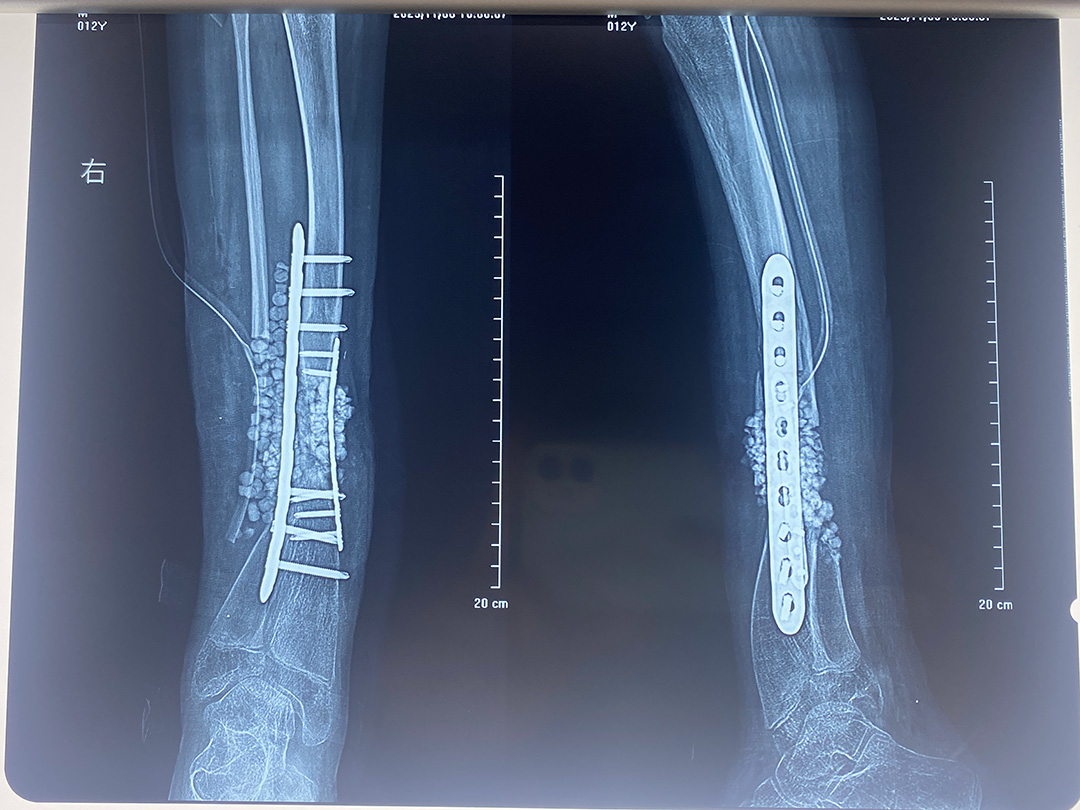

▲术后

面对这一复杂病例,孙杰院长亲自带领骨三科团队,为患者量身定制了精密的手术方案。此次实施的右侧胫腓骨不愈合切开复位植骨内固定 + 人工骨植入 + 跟腱松解术,堪称一套“组合拳”,旨在一次性根治核心问题。手术不仅要矫正骨骼的成角畸形,更要处理陈旧性骨折不愈合的难题,并通过跟腱松解来恢复下肢功能。团队以精湛的技艺成功完成了手术,有效解决了困扰患者多年的骨骼畸形与功能受限问题。

手术取得了圆满成功。术后,患者右侧小腿的力线得以恢复,肢体外观显著改善,重新燃起了站立和行走的信心。这台高难度手术,不仅重塑了少年弯曲的腿骨,更托起了他对未来人生的新希望。它充分展现了周口人合医院骨三科在复杂骨科畸形矫正领域的深厚实力与人文关怀,印证了其为患者骨骼健康保驾护航的不变初心。